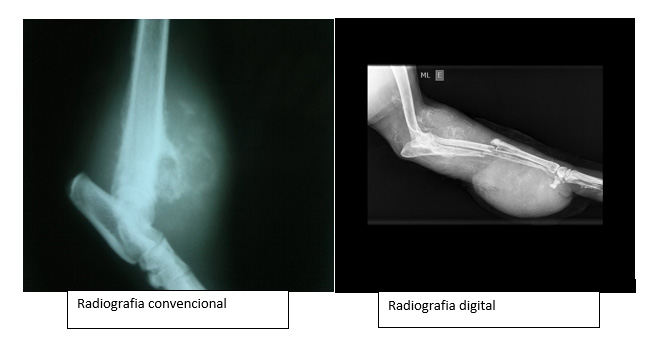

Abaixo serão citadas os tipos, diferenças e vantagens das radiologias convencionais e digitais, explicadas pelo médico veterinário, Fernando Godoy, do do Pet-X Centro Diagnóstico Veterinário.

Nós contamos com a radiologia convencional e, mais recentemente, passamos a dispor da radiologia digital. Esta última constitui um avanço significativo em relação à radiografia tradicional.

No equipamento tradicional o estudo é obtido da sensibilização de um filme comum por meio de raios-X. Na radiologia digital, o filme convencional é substituído por uma película especial, sensível aos raios-X, que é lida por equipamento moderno de computação, o que proporciona uma imagem de alta resolução.

A principal vantagem é a obtenção de imagens de melhor qualidade, o que proporciona maior sensibilidade na detecção de patologias. A radiologia digital é processada em uma estação de trabalho computadorizada, onde temos a possibilidade de processá-la com o uso de sofisticadas técnicas. Com isso temos ainda a possibilidade de fazermos diagnósticos cada vez mais precoces e precisos.